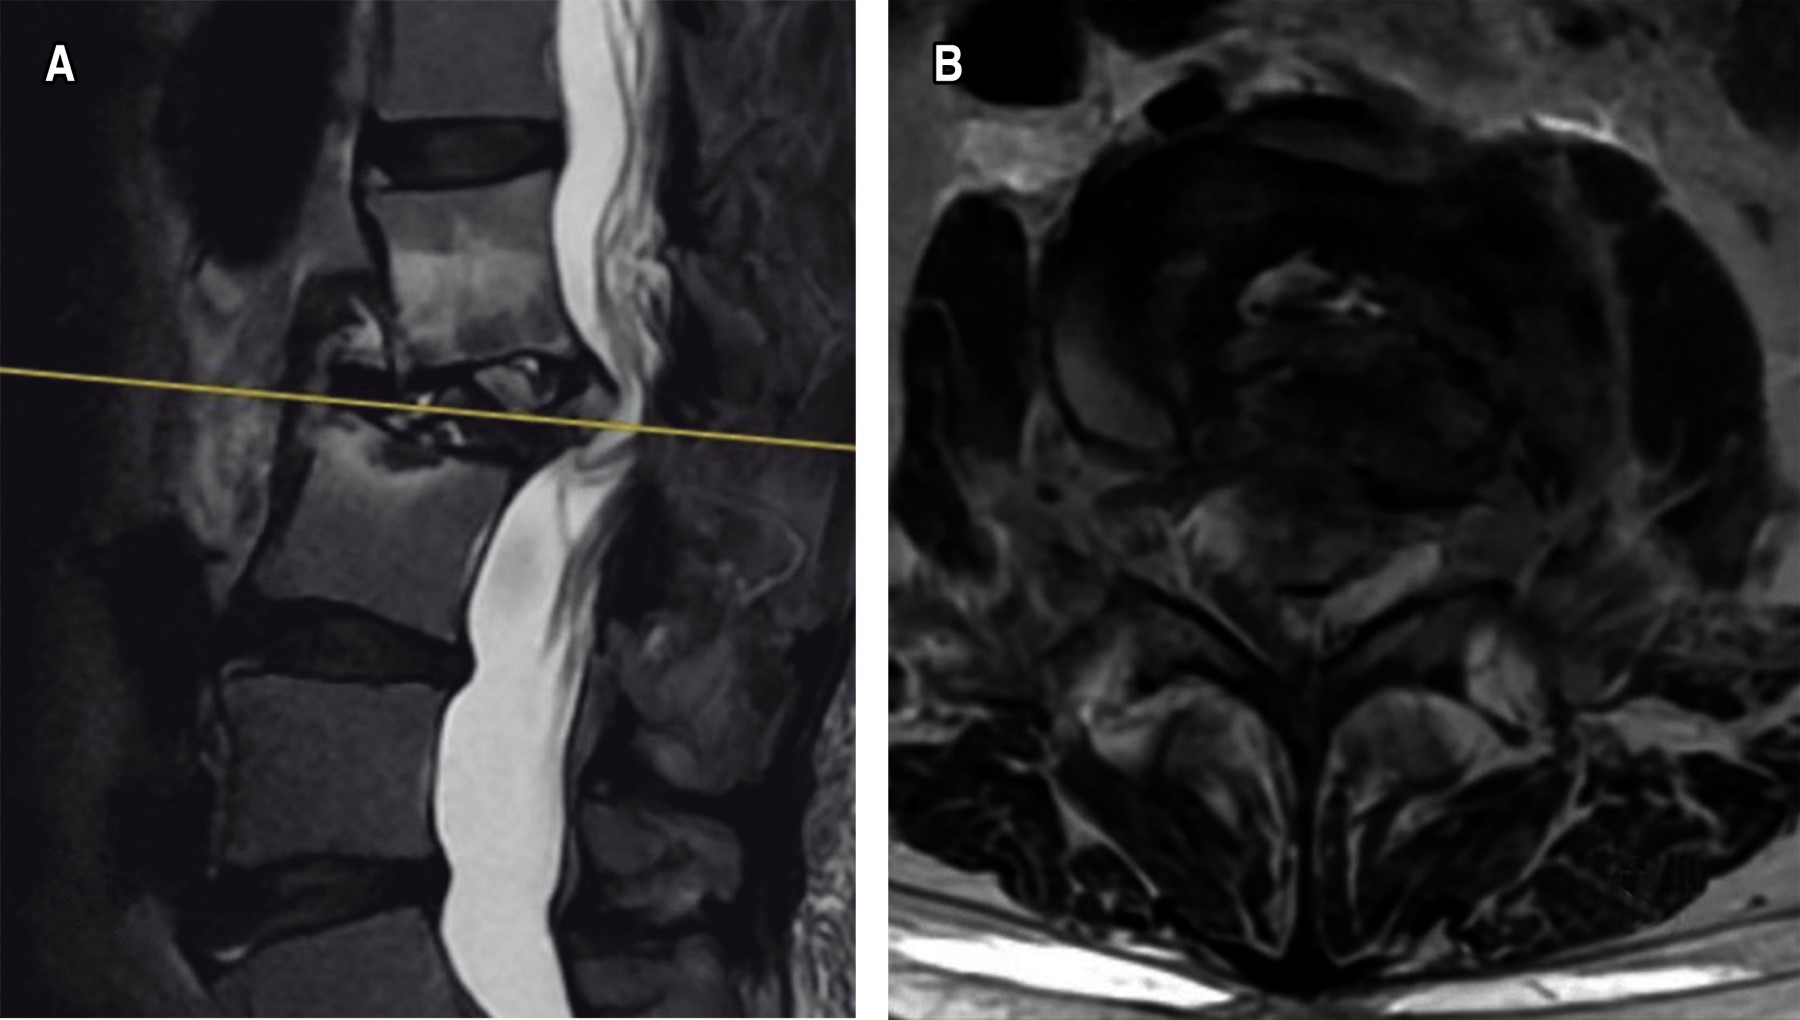

Introduction: brucellosis infection is considered a global public health problem, which is estimated in about 58% of the cases demonstrated with osteoarticular involvement. With a special predilection for involvement of the lumbar spine, in patients with carriers mostly with clear identifiable risk factors. Clinical case: we present the case of a 60-year-old female patient, who began suffering consistent with the presence of pain in the thoracolumbar region of long evolution, with poor response to conservative treatment which shows a progressive intensity, until conditioning loss of ambulation and prostration. A study protocol was performed, in which X-ray and computed axial tomography (CAT) were observed lytic lesion in the vertebral body L2, as well as hyperintense lesions with a tendency to invasion of the spinal canal in axial and sagittal T2 section. Conclusion: brucellosis continues to be an important pathology in our country, in our clinical case a surgical resolution similar to that reported in the international literature was performed, with the topic of the different tools available for such resolution.

Figure 2